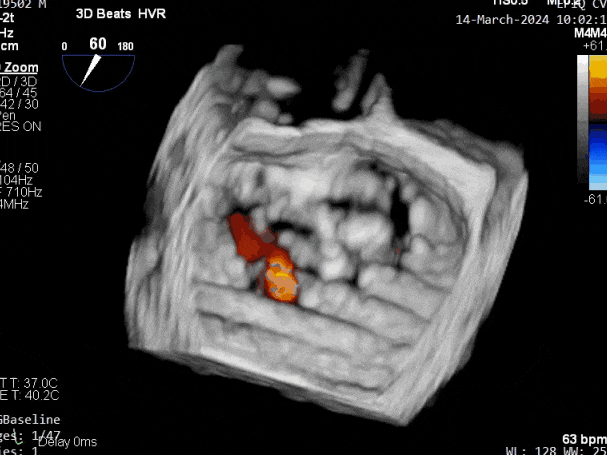

第三个瓣膜夹释放前评估,组织桥张力稳定

第三个瓣膜夹释放前评估,二尖瓣平均跨瓣压差

第三个瓣膜夹释放

第三个瓣膜夹释放后评估,释放后评估,二尖瓣呈双孔,组织桥张力合适,瓣膜夹轴向与二尖瓣闭合线垂直,无残余反流